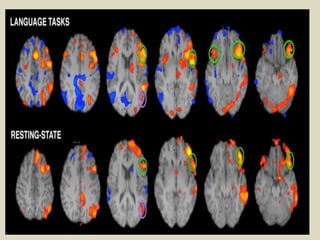

Functional techniques

Functional MRI(fMRI).

Term used to described any technique that evaluates

brain physiology rather than anatomy.

fMRI specifically used to map brain activity .

Areas of interest-motor cortex, visual cortex.

Blood oxygenation level-dependant (BOLD).

BOLD Blood Oxygen Level dependence fMRI I the

most common for research purposes.

Measures the hemodynamic response(amount of

blood flow) related to neural activity in the brain.

Increase in magnetic susceptibility when blood is

oxygenated.

Direct correlation between brain activity and cerebral

blood flow has been observed, but unsure of exact

underlying mechanisms.

Usually uses a T2* weighted contrast.

TR: 2-4s.

2-4 mm spatial resolution(better with 3-9 T).

Although commonly thought of as a directed measure of

brain activity, fMRI usually identifies relative differences

in brain activity.

fMRI is not currently used for diagnostic purposes.

Used to identify functional maps of neural networks &

research relative deficiencies in brain function.

New software allows for the quantification of network

activity via Independent Components Analysis.